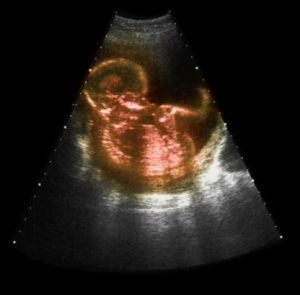

(二)超音波檢查B型超音波測定胎頭位置可確診,並可進一步測定胎頭雙頂徑,了解胎兒的大小,胎頭有無仰伸,有無臍帶繞頸等。

(三)X線檢查如需同時了解骨盆大小者,可作X線檢查協助診斷。

3.外倒轉術:就是醫生用手經孕婦腹壁將胎頭推向骨盆,胎臀推向宮底,使呈頭位的操作。術前應先做B超,了解胎兒發育是否正常,有無臍帶繞頸,胎盤位置,有無胎盤早剝及羊水量多少等。若發現胎兒發育異常、有臍帶繞頸、前置胎盤、羊水過少等情況,則不宜行外倒轉術。